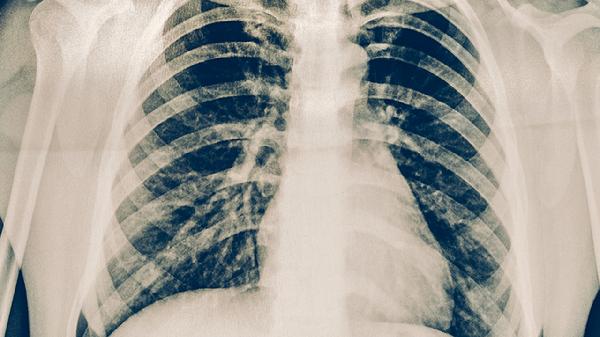

肺癌三代靶向药主要有奥希替尼、阿美替尼、伏美替尼、洛拉替尼、贝福替尼等。这些药物适用于特定基因突变的非小细胞肺癌患者,需在医生指导下使用。

使用三代靶向药前必须进行基因检测确认突变类型,治疗期间每2-3个月复查CT评估疗效。出现严重不良反应如间质性肺病需立即停药。建议患者保持均衡饮食,适量补充优质蛋白和维生素,避免剧烈运动但可进行散步等轻度活动,严格遵医嘱定期复诊。